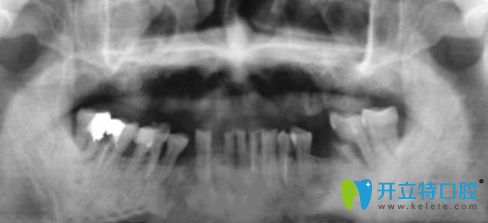

金臺(tái)口腔為張叔拍完X光圖片:

那么,種植牙即拔即種好不好呢?田院長(zhǎng)采用數(shù)字化3D技術(shù),一站式完成牙齒種植流程,不切開(kāi)、創(chuàng)口小、無(wú)需縫合降低腫脹疼痛與不適感。術(shù)后6個(gè)月后牙槽骨和種植體緊密結(jié)合,然后再安裝牙冠。